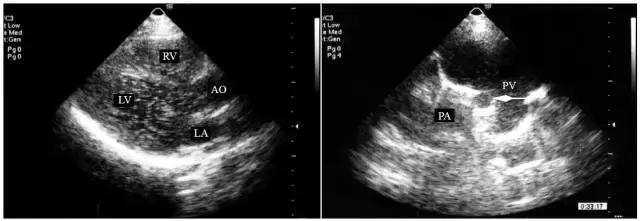

先天性肺动静脉瘘是一种少见的先天性心脏病,小的瘘管只在胸部闻及连续性杂音而无明显的血流动力学改变,也无特征性超声心动图表现,因此肺动静脉瘘的临床主要依靠右心声学造影检查。右心声学造影检查显示造影剂从右心房→右心室→肺动脉→肺静脉→左心房→左心室依次显影,各心腔均充满气泡回声,并可显示微气泡直接从瘘口进入扩张的肺静脉(图9-23-3)。

图9-23-3 肺动静脉瘘的右心声学造影表现

右心声学造影显示肺动静脉瘘时左心房、左心室、右心房和右心室内均充满密集的气泡回声,有时还可在瘘口处显示气泡直接从肺动脉进入肺静脉(箭头所指)(AO-主动脉 LA-左心房 LV-左心室 PA-肺动脉 PV-肺静脉 RV-右心室)